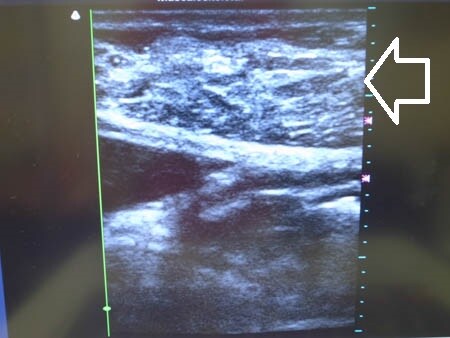

同様に下腹部も見ておきましょう。

↓ ↓ ↓

右横からも状態を比較してみましょう。